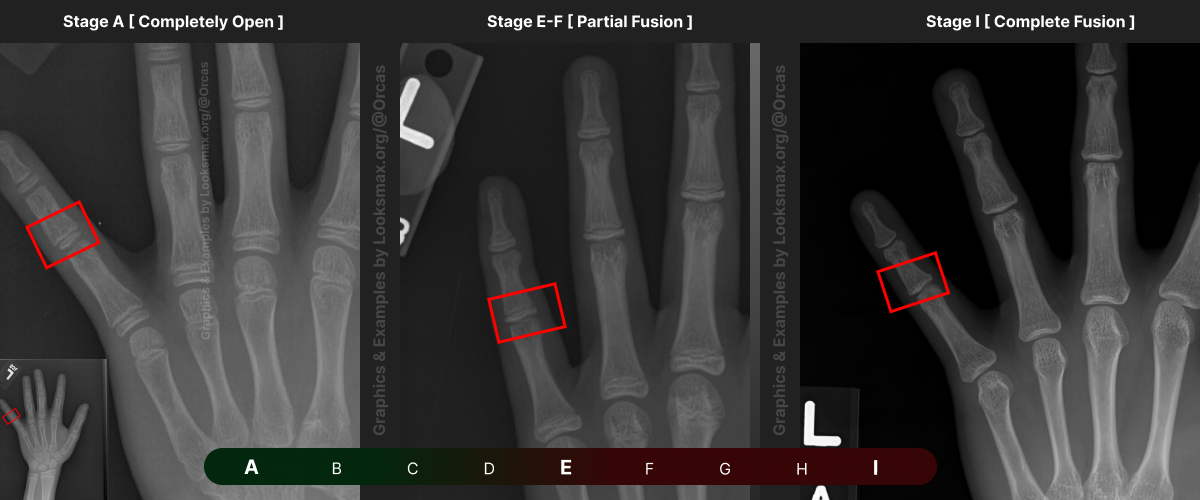

Bonetype: 5th Metacarpal (pinky)

Check & use the chart below to figure out where you are. Then write your result on a piece of paper or a text file.

Bonetype: 5th Proximal Phalanx

Bonetype: 5th Middle Phalanx

I added references for stages A (Completely unfused), E-F (Partial fusion, basically late stages of puberty), and I (Complete Fusion)

You will have to eyeball this now using your own xrays, I’ve given three examples and some wiggle-room for letters using a reference bar (green-red) below the image, write down your estimated guesses in a text file until you finish all 13 bones.